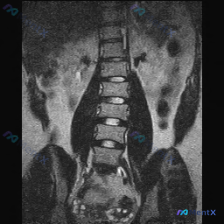

整理到一张腰椎MRI-T2加权冠状位的影像资料,核心发现确实有脊柱侧弯(凹侧指向右侧,胸腰段下为主),但看完分析后觉得,单纯盯着侧弯可能会漏更关键的问题。 先列关键影像表现: 1. 序列:腰椎生理曲度消失,明显侧弯; 2. 椎体:多节段中下段腰椎塌陷、楔形变,边缘骨质增生; 3. 椎间隙:多节段显著...

整理到一份腰椎MRI T1加权像冠状位的影像分析资料,先不说最终倾向,把核心发现放出来大家讨论下: 核心影像表现: 1. 脊柱:明显腰椎右侧凸畸形,椎体边缘骨质增生、部分模糊,椎间隙左右不对称、部分狭窄,椎间盘T1信号广泛减低;小关节间隙窄、关节突肥大,凹侧结构紊乱。 2. 骨髓信号:关键! 椎体骨...